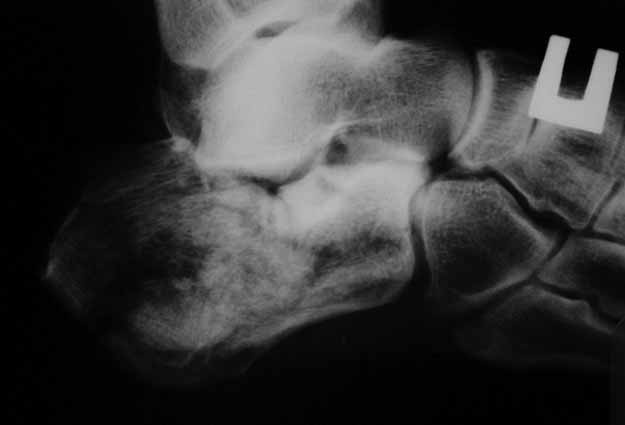

КТ перелома пяточной кости

в замешательство.Прилагаю снимки со дня поступления, августовские пациентом не

представлены.С благодарностью примем советы коллег.